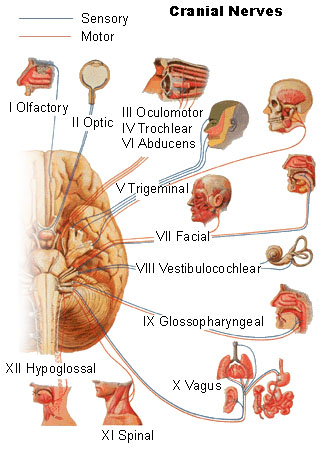

cranial_nerves.html